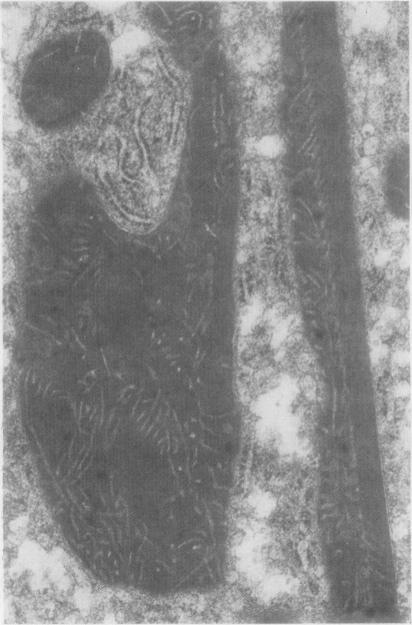

To assess the pattern and severity of liver disease in patients who had undergone jejuno-ileal bypass for the treatment of morbid obesity, 23 patients were biopsied, all of whom had had intact bypasses for more than 10 years. These were examined by light and electron microscopy. Previous biopsy specimens from each patient, including specimens taken before bypass, were reviewed. Similar biopsy specimens were obtained from six obese patients undergoing gastroplasty. There was no evidence of cirrhosis, and mild or moderate degrees of fibrosis were found in only a few patients. Steatosis tended to persist after bypass, albeit to a lesser degree. Giant mitochondria and intramitochondrial filamentous inclusions were present in four of six specimens taken before gastroplasty and in 15 of 23 specimens taken after jejuno-ileal bypass, being especially numerous in those specimens showing little or no steatosis. It is suggested that such features reflect ultrastructural evidence of adaptation to an abnormal metabolic environment both in the morbidly obese and even many years after jejuno-ileal bypass. Their prognostic importance is unclear.

为评估接受空肠回肠分流术治疗病态肥胖症患者的肝脏疾病模式及严重程度,对23例患者进行了活检,所有患者的分流术均保持完整且已超过10年。对这些患者的活检组织进行了光镜和电镜检查。回顾了每位患者之前的活检标本,包括分流术前采集的标本。从6例接受胃成形术的肥胖患者中获取了类似的活检标本。未发现肝硬化证据,仅少数患者存在轻度或中度纤维化。分流术后脂肪变性往往持续存在,尽管程度较轻。胃成形术前采集的6份标本中有4份、空肠回肠分流术后采集的23份标本中有15份存在巨大线粒体和线粒体内丝状包涵体,在那些几乎没有或没有脂肪变性的标本中尤其多见。提示这些特征反映了病态肥胖患者以及空肠回肠分流术后多年对异常代谢环境适应的超微结构证据。其预后重要性尚不清楚。